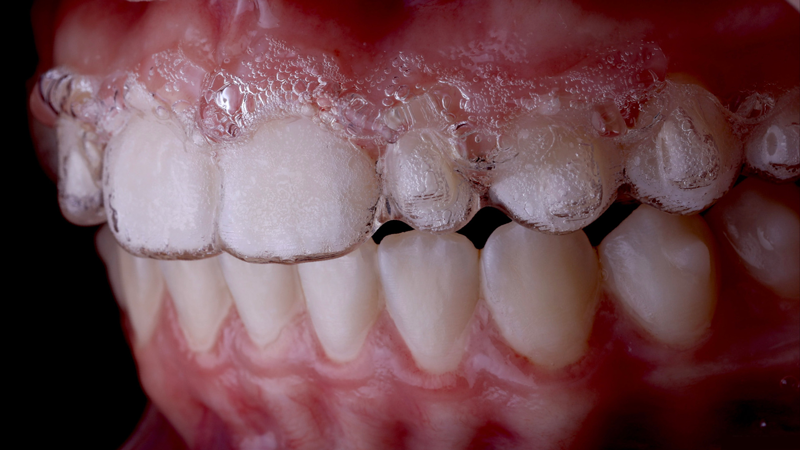

Fig 6. Clear aligners may serve a dual purpose as a

custom-fit bleaching tray. In addition, the patient benefits from the antibacterial properties and beneficial cariostatic effects of the urea byproduct

in 10% carbamide peroxide when the custom-fit tray (ie, the aligners) is allowed to remain in contact with the gingiva overnight.

Clear aligner therapy, and to a lesser extent conventional bonded brackets and archwires, are routine orthodontic treatments for many adolescent patients. Both modalities possess potential drawbacks to optimal oral health. Aligners, for example, rely on the use of composite resin attachments, or "buttons," to aid in the movement of the teeth (Figure 5). These attachments are porous and usually possess an irregular shape, which may adversely affect the patient's oral hygiene. When used in combination with 10% carbamide peroxide gel, the aligners serve as a well-adapted custom-fit tray (Figure 6).24 For the patient younger than age 18 years, carbamide peroxide is also an ideal bleaching agent because of the antibacterial properties and beneficial cario- static effects that the urea byproduct has on gingival health scores.20 In order to achieve the maximum oral health benefits, the aligners containing the whitening gel should ideally be worn overnight or for up to 10 hours.18